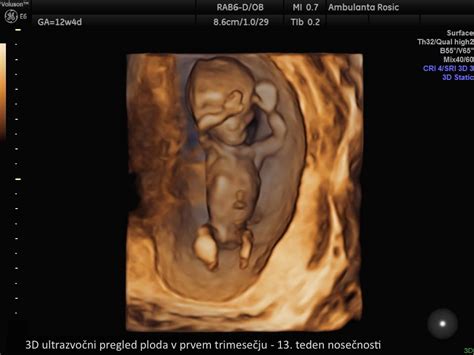

V tem obdobju pride do izjemnega napredka v razvoju ploda. Ob začetku drugega trimesečja, v 13. tednu, meri plod približno 12 cm in tehta okoli 20 gramov. Vendar pa se ta majhna bitja hitro spreminjajo. Do konca 26. tedna se njegova dolžina potrojí na približno 30 cm, teža pa naraste na kar 650 gramov.

Že v 13. tednu je otrok povsem razvit v svoji osnovni obliki, vendar sledijo pomembne funkcionalne izboljšave. V 14. tednu se izrazito poveča njegova teža, kar je znak hitre rasti. Vse glavne mišične skupine se že odzivajo na dražljaje iz možganov. Plod lahko upogiba roke v zapestju in komolcu, prste na roki lahko stisne v pest. Zanimivo je, da je v tem času že sposoben razviti pogojne reflekse, kar nakazuje na sposobnost učenja. To govori o dokaj razviti možganski skorji, spominu in delovanju živčnih poti, ki povezujejo organe in mišice.